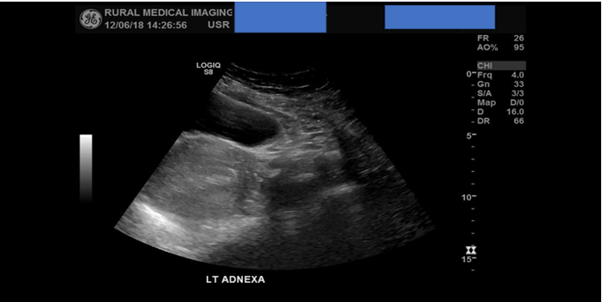

A scan of the left adnexa in the transverse plane from inferior to superior concluded that no pathology was detected but failed to observe the left ovary. A second sweep now of the right adnexa observed a well-defined anechoic lesion near the interstitial fallopian tube region. A possible GS was suspected, no obvious yolk sac or foetal pole was detected within the lesion. Literature states that the risk of an EP can exceed 90% when there is no detectible IUP and there is a corresponding adnexal lesion present. [1]

Figure 2: TAS of the left adnexa concluded no obvious pathology detected but failed to detect the left ovary.